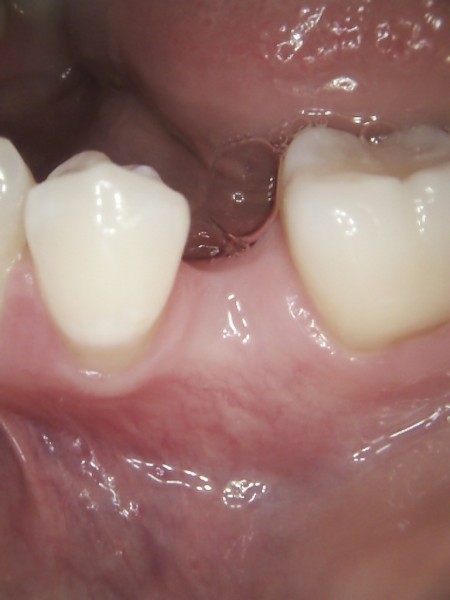

What can I do to replace my missing teeth?

Teeth may be lost or removed due to severe decay, gum disease, fracture or traumatic injury. When a tooth is lost, the surrounding and opposing teeth can shift and move towards the now open space. These changes are slow to take place, but can eventually lead to an increased risk of tooth decay, gum disease, excessive wearing and jaw joint problems. The jaw bone around the lost tooth will also start to shrink away which can lead to changes in the facial appearance in that area. In addition to this, missing teeth means a loss of function as well as possible cosmetic problems.

Missing teeth can be replaced with:

- Removable partial dentures/plates

- Fixed bridge

- Implant supported tooth/bridge

If you have missing teeth, ask us what your options may be to replace them in order to prevent potential long term problems.